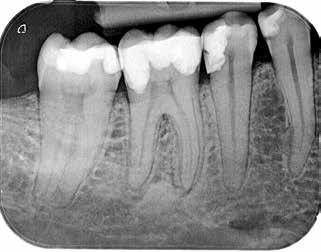

B.

der viser en lille, men tydelig radiolucens (pil) I relation til den ikke-rodfyldte 6-. Hvis der kan ses en radiolucens, er der sandsynligvis apikal parodontitis til stede. Det intraorale radiologiske billede underestimerer ofte læsionens omfang (Bender, 1982)

Fig. 2. A. Bite-wing radiograph showing deep caries in tooth 36, but with dentin visible between lesion and pulp (arrow). In such cases, the pulpal inflammation is usually reversible, and treatment should aim to preserve pulp vitality (Bjørndal et al., 2010).

B. Intraoral periapical image showing a small but clear radiolucency (arrow) associated with the non-root-filled tooth 46. If a radiolucency is visible, apical periodontitis is likely present. The intraoral radiographic appearance often underestimates the extension of the lesion (Bender, 1982)